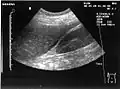

Ultrasound of liver (left side of the image) and right kidney (right side of the image) and Morison's pouch, not containing fluid -